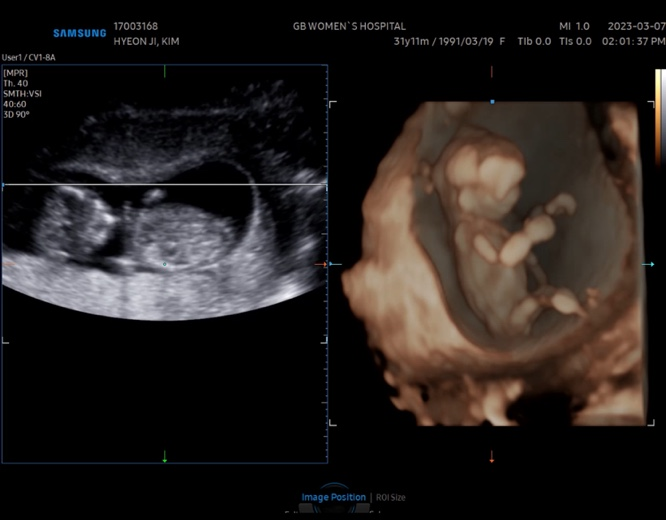

[임신 기록 7] 임신 16주 차 증상 _ 2차 기형아 검사(성별 확인&조리원 예약) / 철분제 볼그레 복용 / 주수 원피스 구입

임신 16주 차 기록 ・ᴥ・♥ ✿ 달라진 배 크기, 주수 원피스 구입 ✿ 12주 차부터 주수 사진을 찍고 싶었...